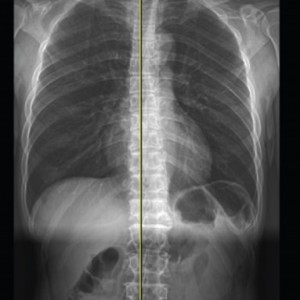

Before & After

해당 사진은 수정없는 실제 치료사진입니다.

환자의 치료결과는 환자의 상태, 치료방법 등에 따라 차이가 발생할 수 있습니다.